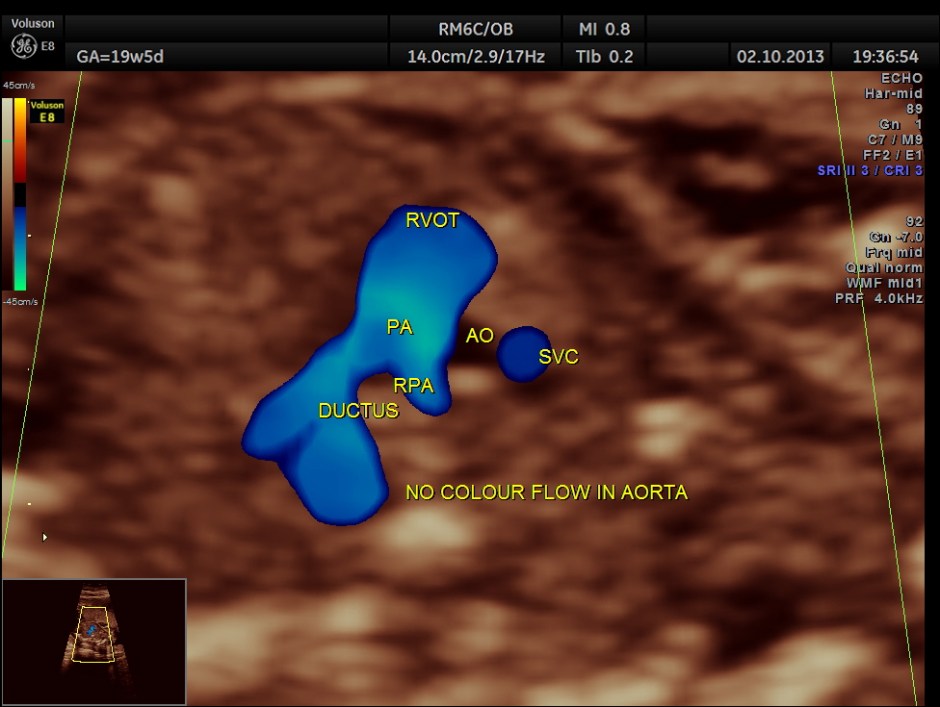

The 3 vessel trachea view depicts great vessel disproportion. Pulmonary artery is bigger than aorta .

Colour flow also rules out the possibility of hypoplastic left heart syndrome.